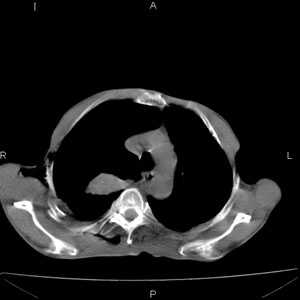

患者男,77岁,于3日前从树上摔下,头部查ct示蛛血,硬膜下出血,上腹部ct未见明显异常,右侧胸腔积液,左侧如常。肺部拍片示右侧肋骨多发骨折住院后今日来查肺部ct,我看到的是1。右侧胸腔血气胸并右肺上叶,中叶压缩性肺不张,2。右肺下叶肺挫伤并多发肋骨骨折,肌内及皮下积气3。左侧少量胸腔积液,我想请教的是3天前左侧胸腔里没有积液今天怎么出现了呢,是什么原因呢?请讨论。